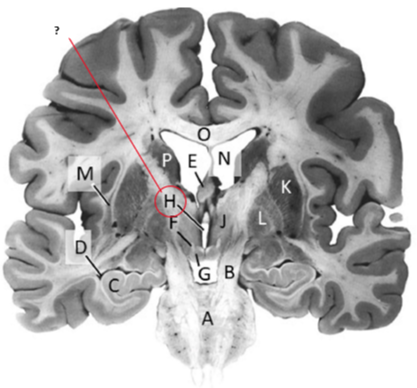

Name this and state its function.

Thalamus.

Name this ,state its function and the name of the structures closely associated with it.

Putamen.

Name this, state its function and its components[4 marks].

Globus Pallidus.

Claustrum.

Name.

Temporal horn of lateral ventricle.